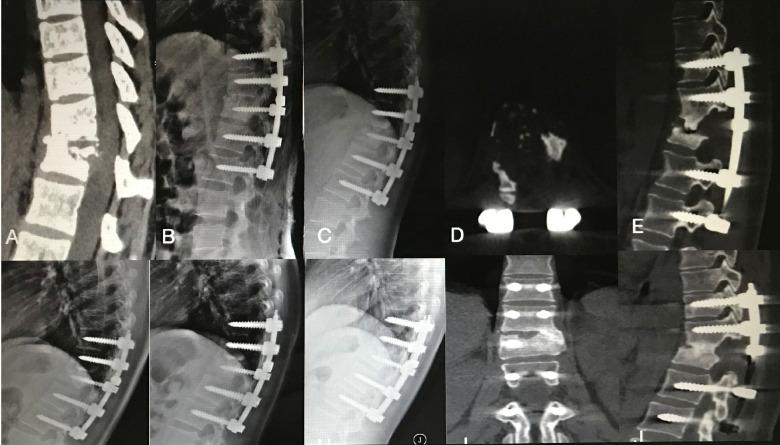

A retrospective study investigated and compared the results of lamina with spinous process (LSP), transverse process strut (TPS) and iliac graft (IG) as bone graft in thoracic single-segment spinal tuberculosis(TB) with the one-stage posterior approach of debridement, fusion and internal instrumentation. 99 patients treated from January 2012 to December 2015 were reviewed. LSP was performed in 35 patients (group A), TPS was undertaken in 33 patients (group B), and IG was carried out in 31 patients (group C). Surgical time, blood loss, hospitalization time, drainage volume, and follow-up (FU) duration were recorded. The visual analog scale (VAS), Oswestry Disability Index (ODI), erythrocyte sedimentation rate (ESR), C-reactive protein (CRP), American Spinal Injury Association (ASIA) grade, segmental angle, intervertebral height and bone fusion time were compared between preoperative and final FU. All the patients were followed up for a mean 43.90±10.39 months in group A, 45.30±6.20 months in group B, 44.32±7.17 months in group C without difference(>0.05). The mean age was younger, the blood loss was less, the hospitalization time and the surgical time were shorter in group A than those in group B and C (<0.05). The drainage volume was less in group A than that in group B and group C. The CRP, ESR, VAS, and ODI were significantly decreased and there were no significant difference among the groups at the final FU. The neurological function after surgery was improved compared with preoperation among the groups. The bony fusion at a mean time 12.90±3.91 months in group A was longer than that in group B (6.75±1.55 months) and group C (5.52±1.64 months) (<0.05). No significant difference was found at the mean segmental angle, mean intervetebral height of preoperation and final FU among the groups (>0.05). In conclusion, the LSP and TPS as bone graft are reliable, safe, and effective for single-segment stability reconstruction for surgical management of thoracic TB and TPS could be new bone graft methods.